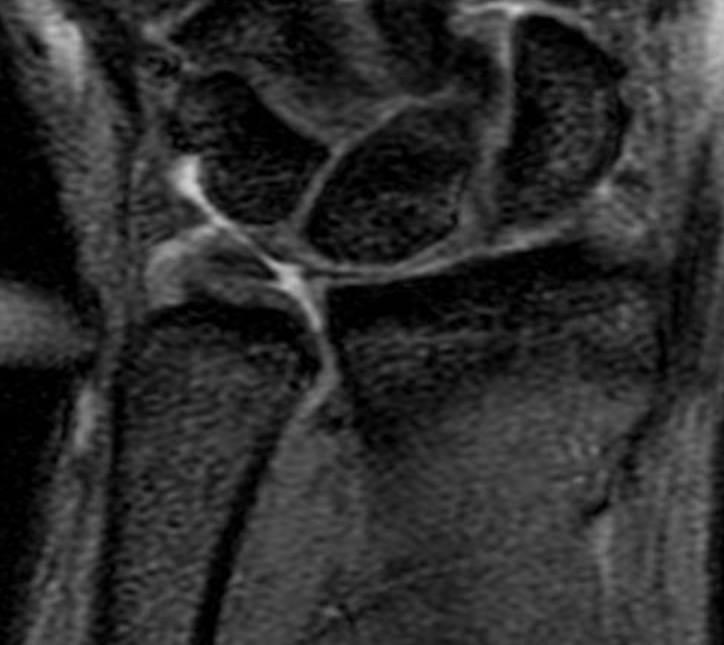

MRI

Normal

TFCC tears

Ulna sided tear

Radial sided TFCC tear

Central TFCC tear

Ulno-carpal abutment

Ulnocarpal abutment and lunate chondromalacia

Ulna positive with ulnocarpal osteoarthritis